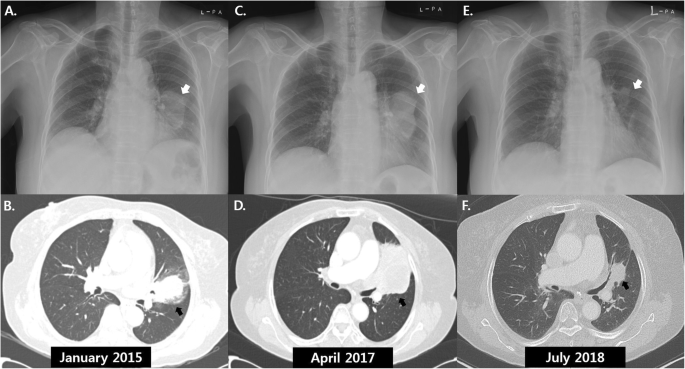

Берлинская конференция, собравшая врачей и учёных из разных уголков мира, освещает этот феномен с научной точки зрения. Участники обсуждают реальные случаи спонтанной ремиссии, подходя к делу с полной строгостью. Все представленные данные проходят тщательную проверку — от гистологических заключений до результатам МРТ и КТ. Это исключает любые ошибки и позволяет сосредоточиться на фактах, а не на мифах.